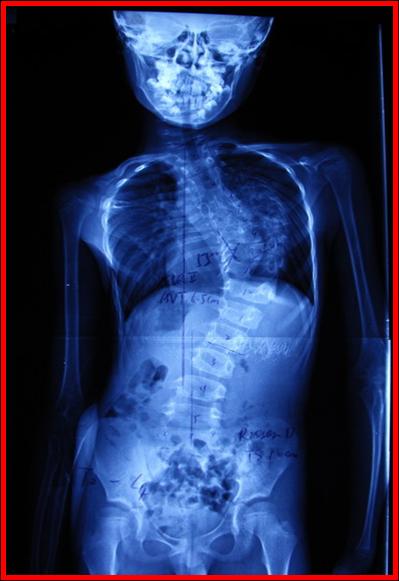

术前X线